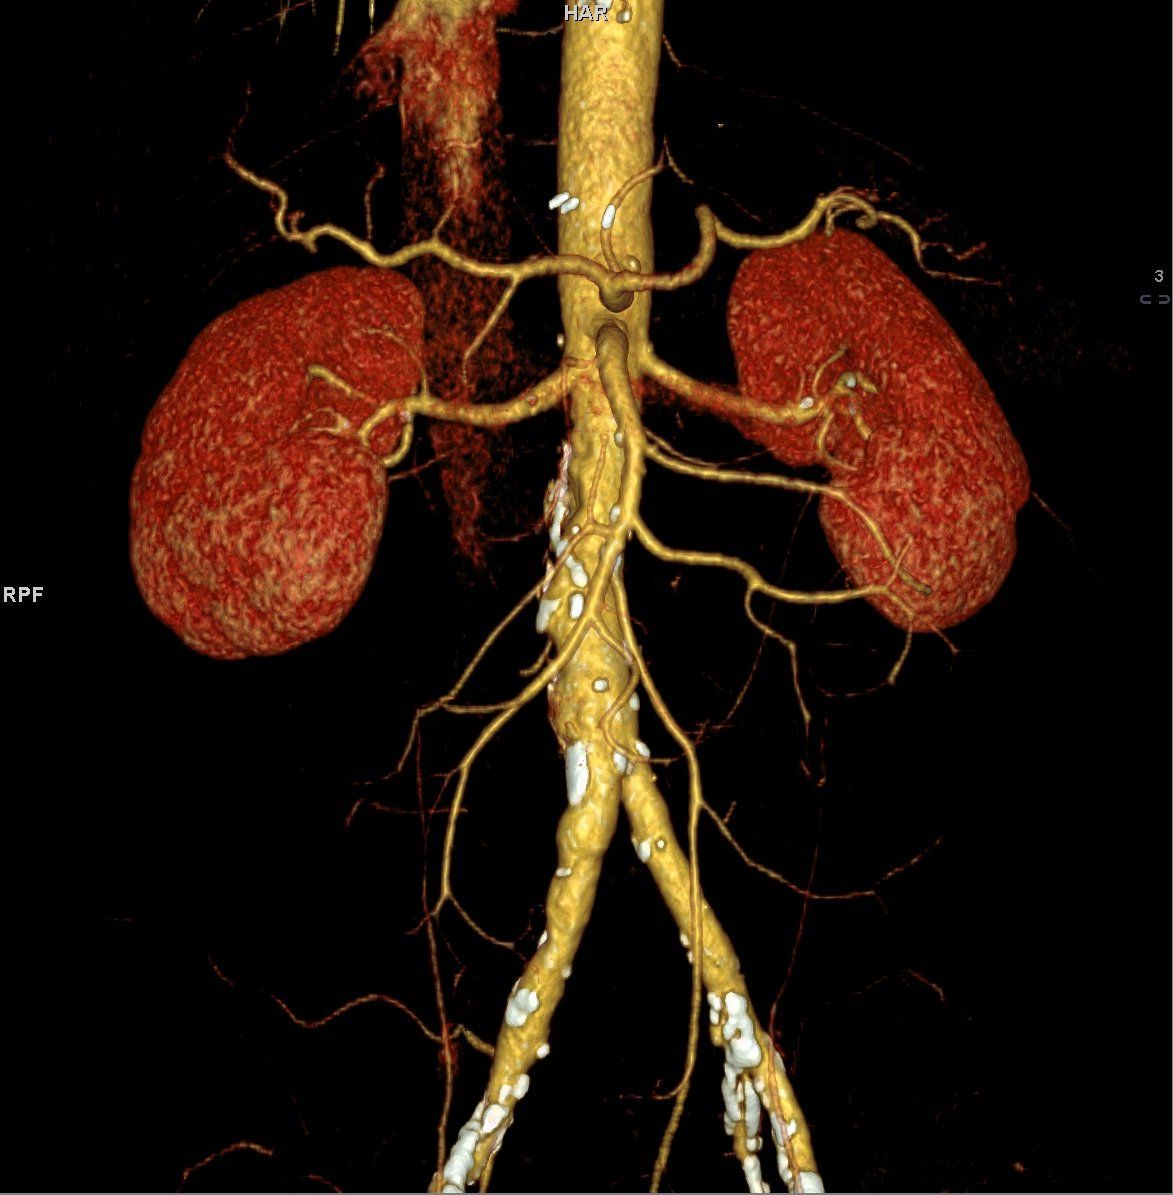

Consulter un médecin en cas de fracture ou en cas de suspicion lui permettra de vous demander de réaliser un examen complémentaire dans le but de confirmer et de localiser la lésion. Notre centre

est équipé avec des équipements de pointe ce qui vous permettra de ne pas perdre de temps et réaliser votre examen sans plus attendre.

La réalisation d'un scanner peut être nécessaire également dans les cas de suspicion d'une tumeur, cancer, lésion interne, etc.